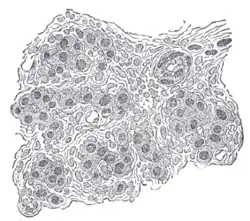

Section of part of human carotid body. Highly magnified. Numerous blood vessels are seen in section among the cells.

The carotid body is a small cluster of chemoreceptor cells and supporting sustentacular cells situated at bifurcation of each common carotid artery in its adventitia.[1][2]

The carotid body is made up of two types of cells, called glomus cells: glomus type I cells are peripheral chemoreceptors, and glomus type II cells are sustentacular supportive cells.